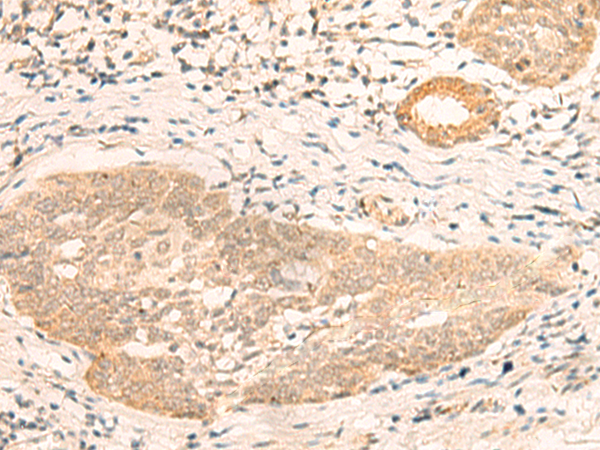

IHC positive control: |

Human cervical cancer and Human esophagus cancer |

ELISA, IHC |